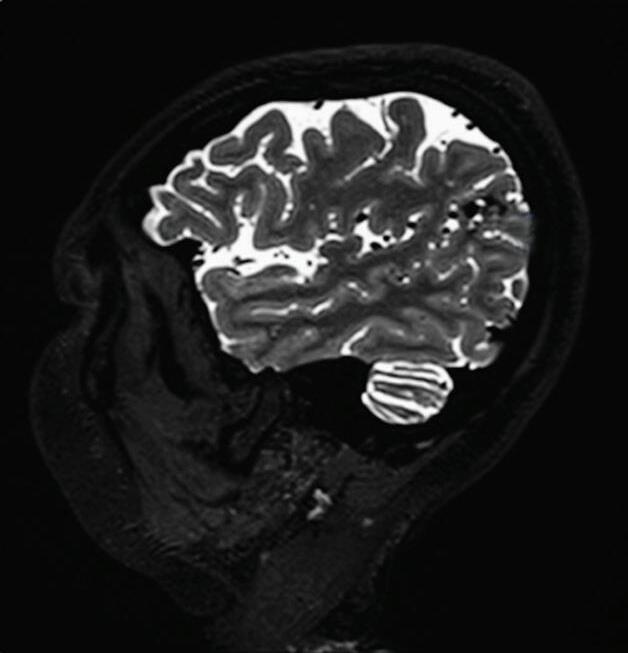

Fig. 1-8. (a-c) RNM T1 com contraste, cortes sagital (a), coronal (b) e axial (c) demonstrando MAV não rota com nidus localizado no lobo occipital à esquerda (setas longas). (d) Arteriografia digital cerebral com injeção de contraste via carótida direita (AP) mostrando a contribuição da carótida direita na irrigação da MAV contralateral. (e,f) Com injeção de contraste via carótida esquerda, em Perfil e AP respectivamente, observa-se nidus compacto nutrido por ramos da artéria cerebral média à esquerda e a veia de drenagem precoce se dirigindo para o seio sagital superior. Projeções em AP (g) e em perfil (h) demonstrando a contribuição do sistema vertebrobasilar por meio de ramos distais da artéria cerebral posterior à esquerda e drenagem para os seios sagital superior e sigmoide à esquerda (setas curtas).